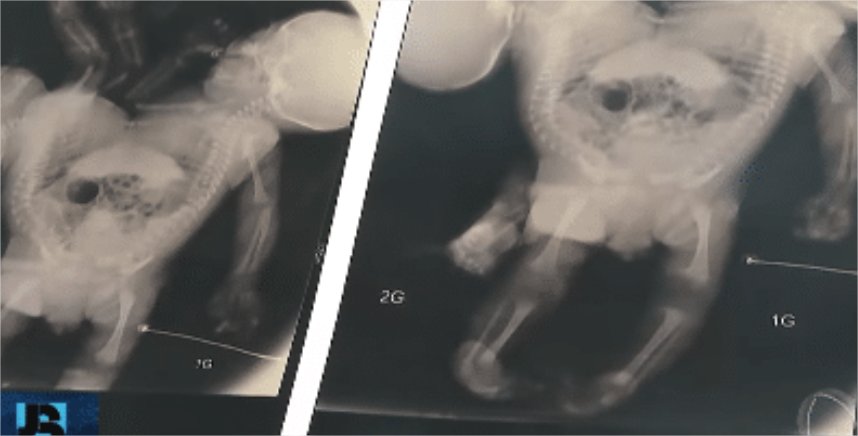

Os recém-nascidos são classificados como isquiópagos, unidos pelo tórax, abdômen, bacia e pernas. “O fígado é único, a bacia também é única, nós não sabemos ainda como é que é a parte urinária da bexiga, se elas são unidas, separadas”, explicou, ao Jornal da Record, o médico Zacarias Calil, que já atuou no parto de 46 bebês siameses e na separação de 25.

Nos próximos dias, os irmãos passarão por uma nova intervenção cirúrgica para corrigir uma má formação no intestino. A complexidade da futura separação exige um longo período de preparo. “A cirurgia de separação dos gêmeos pode acontecer daqui um ano, de acordo com os médicos, dependendo do desenvolvimento das crianças”, informou o hospital.